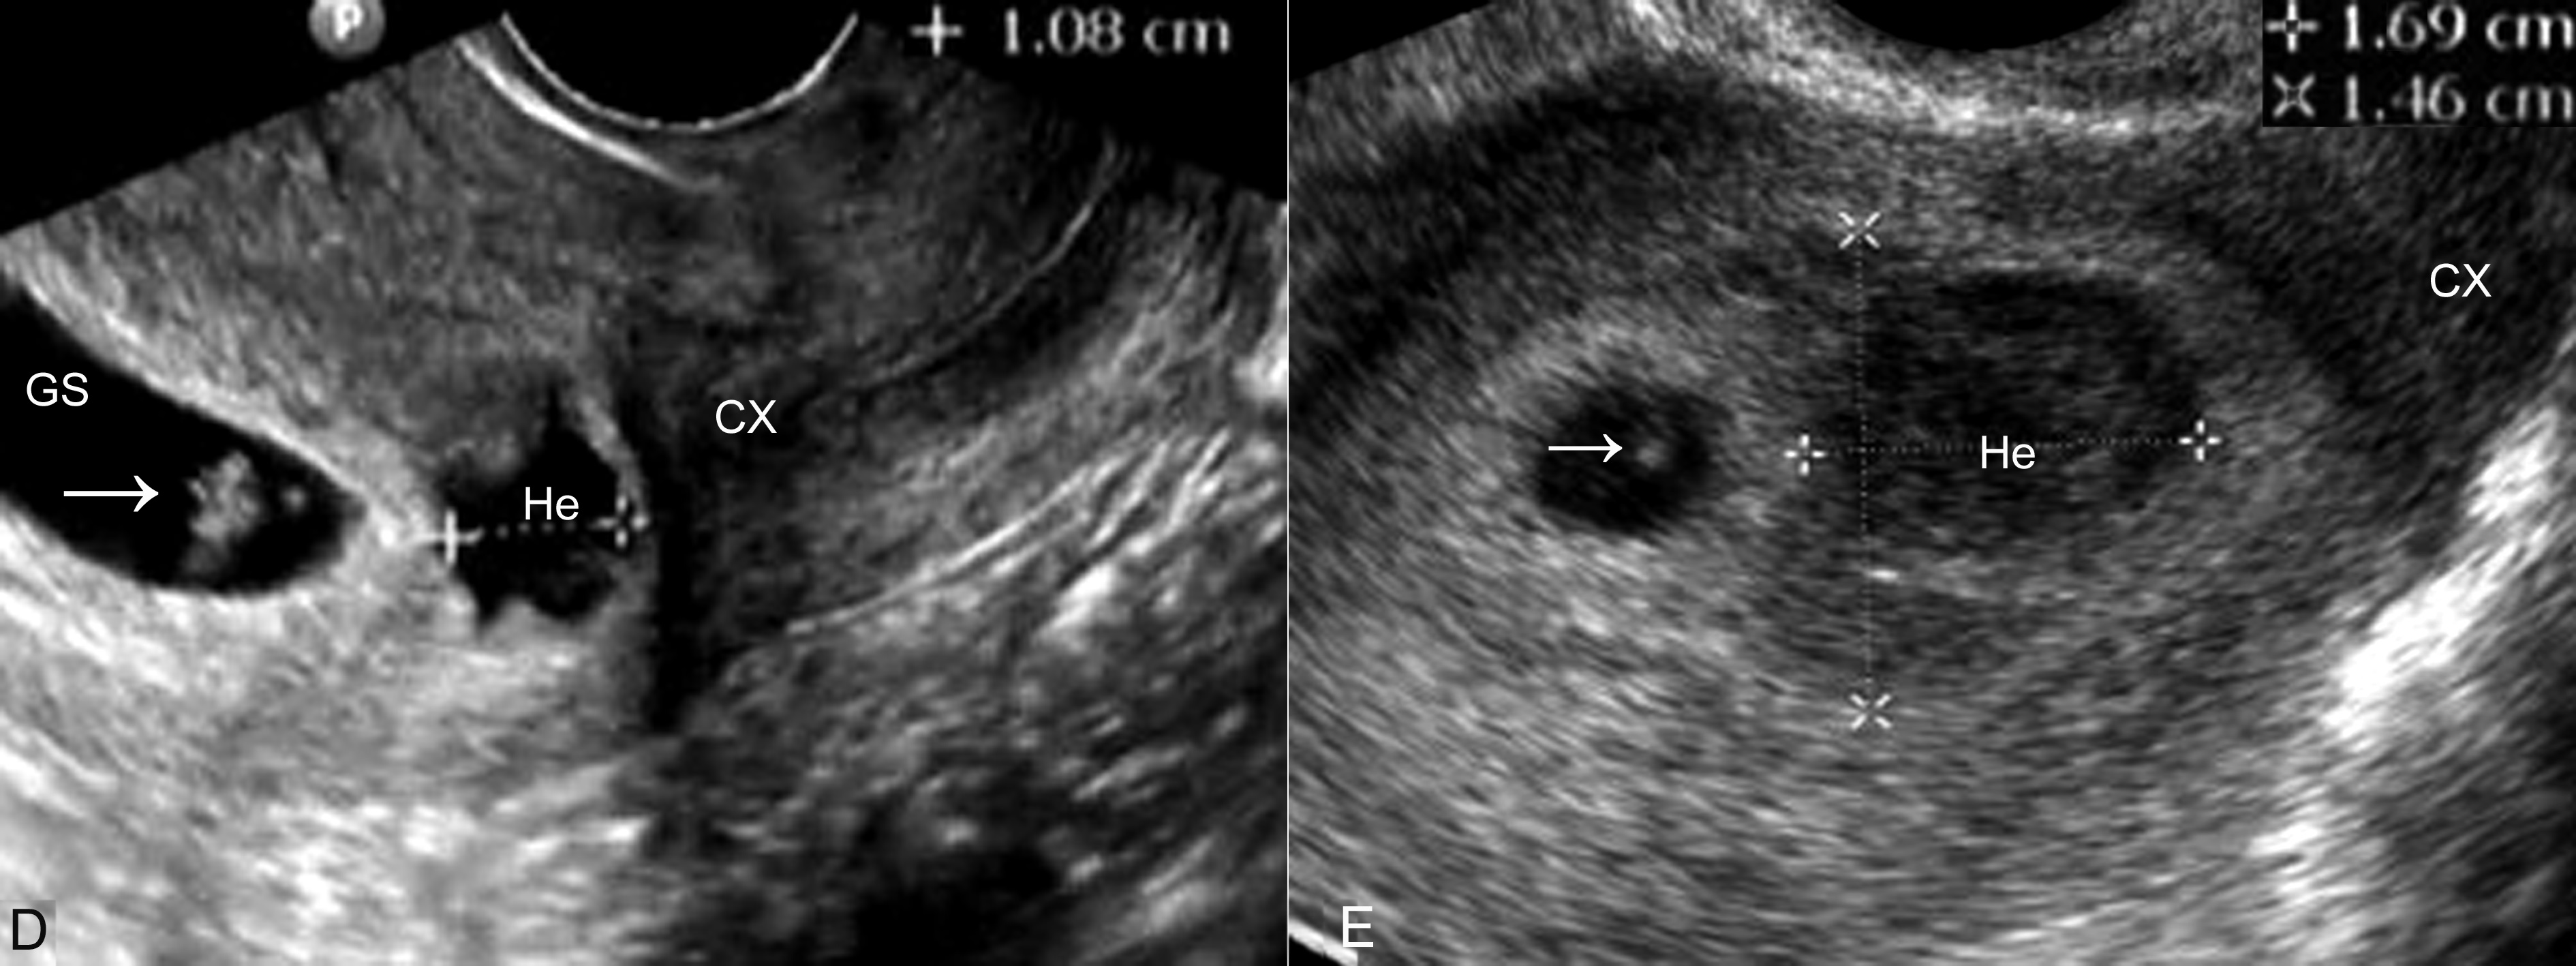

妊娠囊大小正常或较正常缩小,位置下移、变形(图3A)、边缘失去连续性;内部胚胎或胎儿活动消失,心脏搏动明显变弱或不规律、或消失(图3B);如果绒毛膜下血肿超过15ml以上并波及胎盘基底部,即便没有孕囊移位和胚胎死亡,多数也将以流产结束妊娠。

图3 难免流产声象图:变形的孕囊(GS)